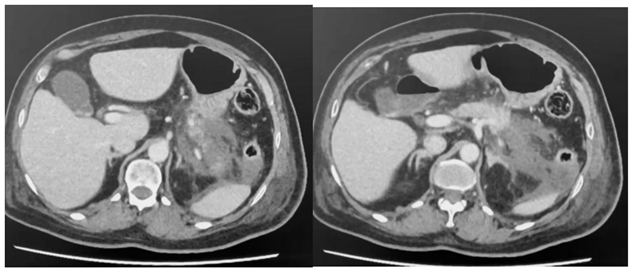

Paciente com pancreatite aguda que necessitou durante 36 h de droga vasoativa no início de tratamento, realizou a tomografia com contraste endovenoso no quinto dia de internação, conforme abaixo.

De acordo com as informações e tomografia acima, assinale a alternativa correta.